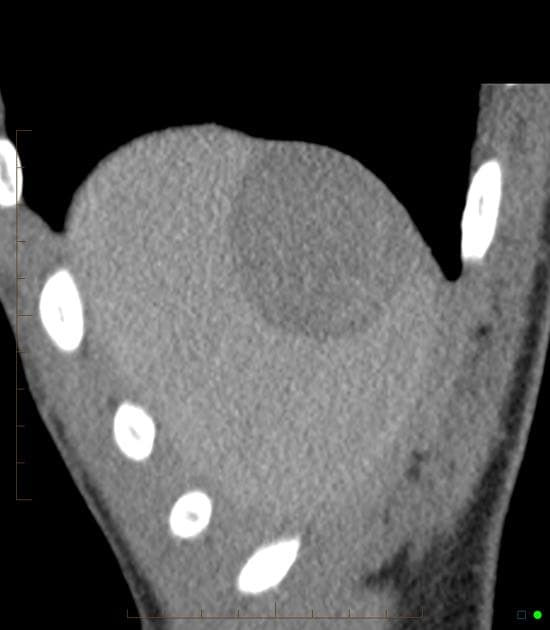

Chụp cộng hưởng từ ổ bụng (abdominal MRI)

- Tổn thương dạng thùy (lobulated) ở thuỳ gan phải, chủ yếu tại các phân đoạn 7 và 8.

- Tổn thương có những vùng tăng tín hiệu (hyperintense) nhẹ so với nhu mô gan trên hình ảnh T1 trước tiêm thuốc, phù hợp với xuất huyết (hemorrhage).

- Không thấy mỡ nội tại (gross lipid content) trong tổn thương.

- Khối tổn thương tăng quang ở thì động mạch, dạng thùy, tại thuỳ gan phải, chủ yếu ở các phân đoạn 8 và 7.

- Tín hiệu của khối giảm xuống mức nền trên các thì trễ (fades to background signal intensity on delayed sequences).

- Không thấy hiện tượng washout.

- Không thấy hình thành giả màng bao (pseudocapsule formation).

Bệnh nhân đã được thực hiện cắt bỏ gan phải (right hepatectomy): chẩn đoán bệnh lý là u tuyến gan (hepatic adenoma), phù hợp với hình ảnh MRI.

U tuyến gan (hepatic adenoma) – phức tạp do xuất huyết (complicated by hemorrhage)

U tuyến gan là một khối u lành tính ở gan, thường gặp ở người trẻ tuổi, đặc biệt là phụ nữ sử dụng thuốc tránh thai đường uống. Khối u có thể gây đau bụng cấp tính do xuất huyết trong khối u như trường hợp này. Trên cộng hưởng từ, u tuyến gan thường hiện diện như khối u dạng thùy, tăng quang mạnh ở thì động mạch, không có hiện tượng washout hay hình thành giả màng bao – giúp phân biệt với ung thư biểu mô tế bào gan. Tín hiệu tăng trên T1 do xuất huyết và không chứa mỡ là các đặc điểm hình ảnh quan trọng. Điều trị bao gồm cắt bỏ phẫu thuật đối với các u lớn (>5 cm) hoặc có biến chứng như xuất huyết để ngăn ngừa vỡ và chuyển ác.